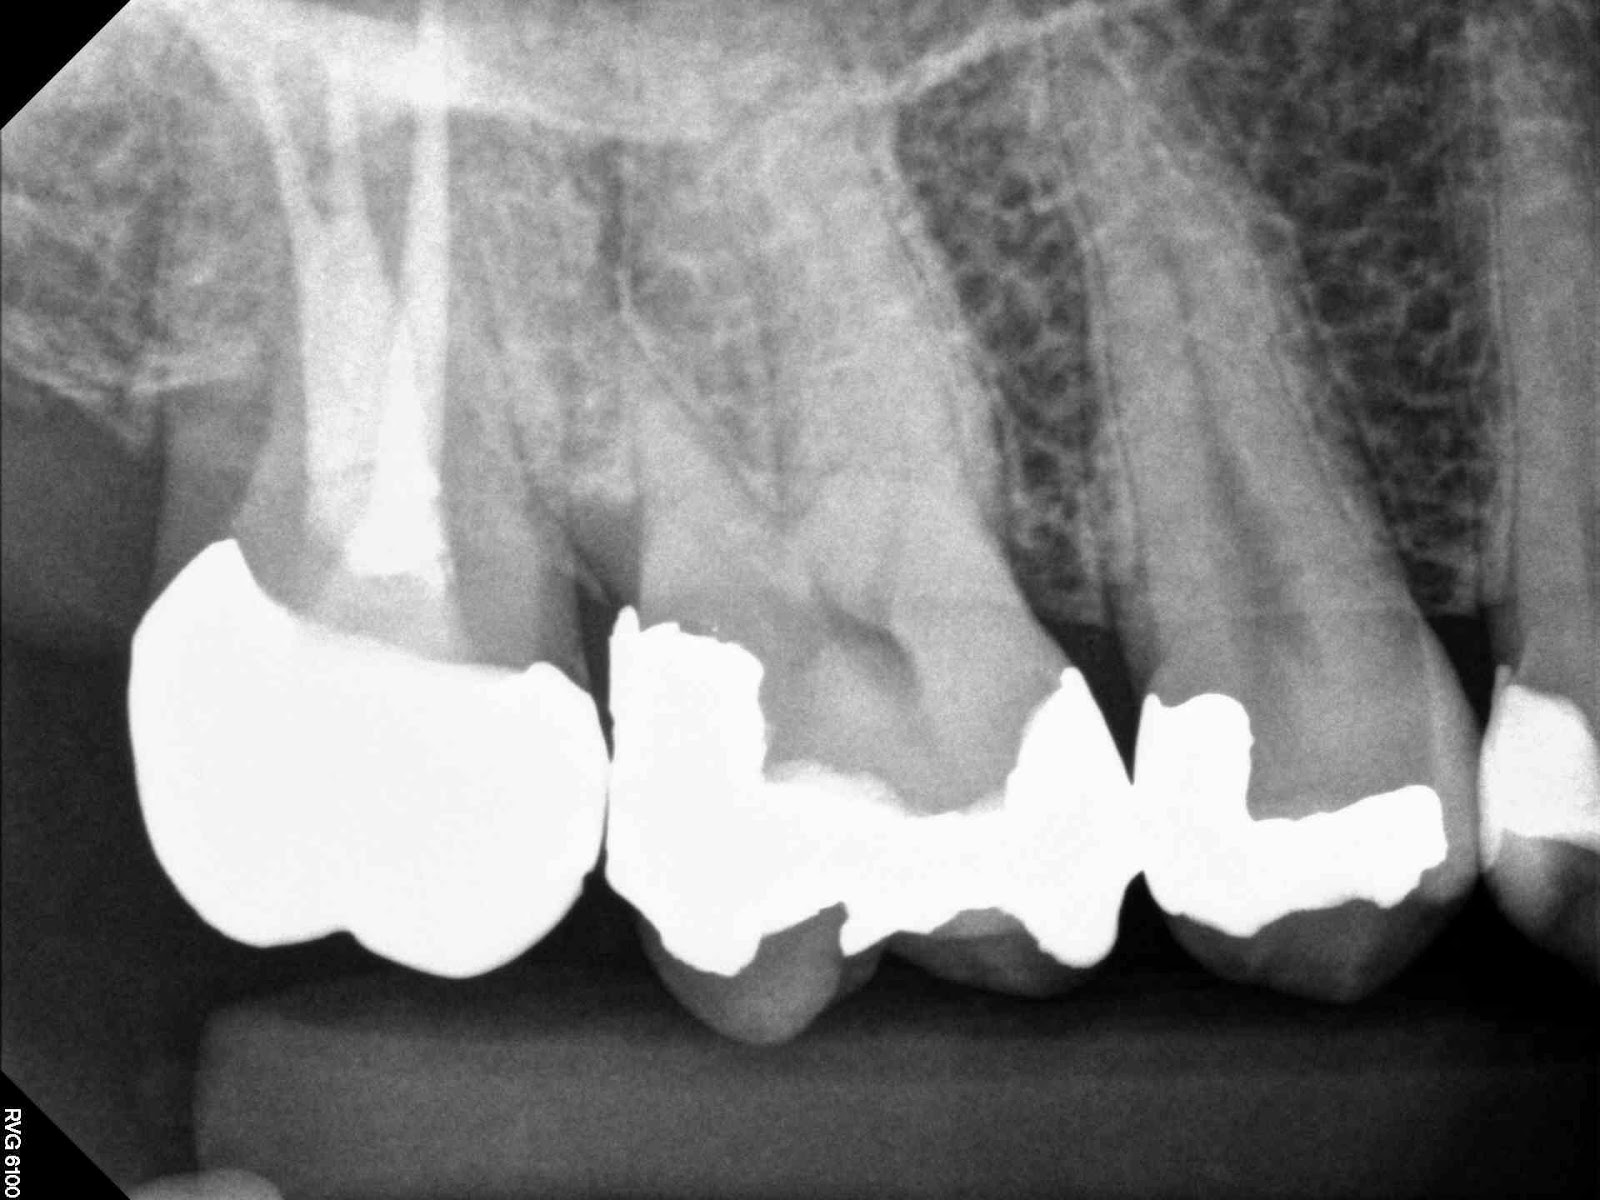

Tooth vital – tooth necrotic

# teeth with MB2 present- able to cleanse and shape the MB2 – MB2 join

MB1 – teeth I consider calcified that no MB2 was found – total # of 1st

molar treated

MB2 distance from MB1 – join MB1

10-11=21

17-14-7-0-21